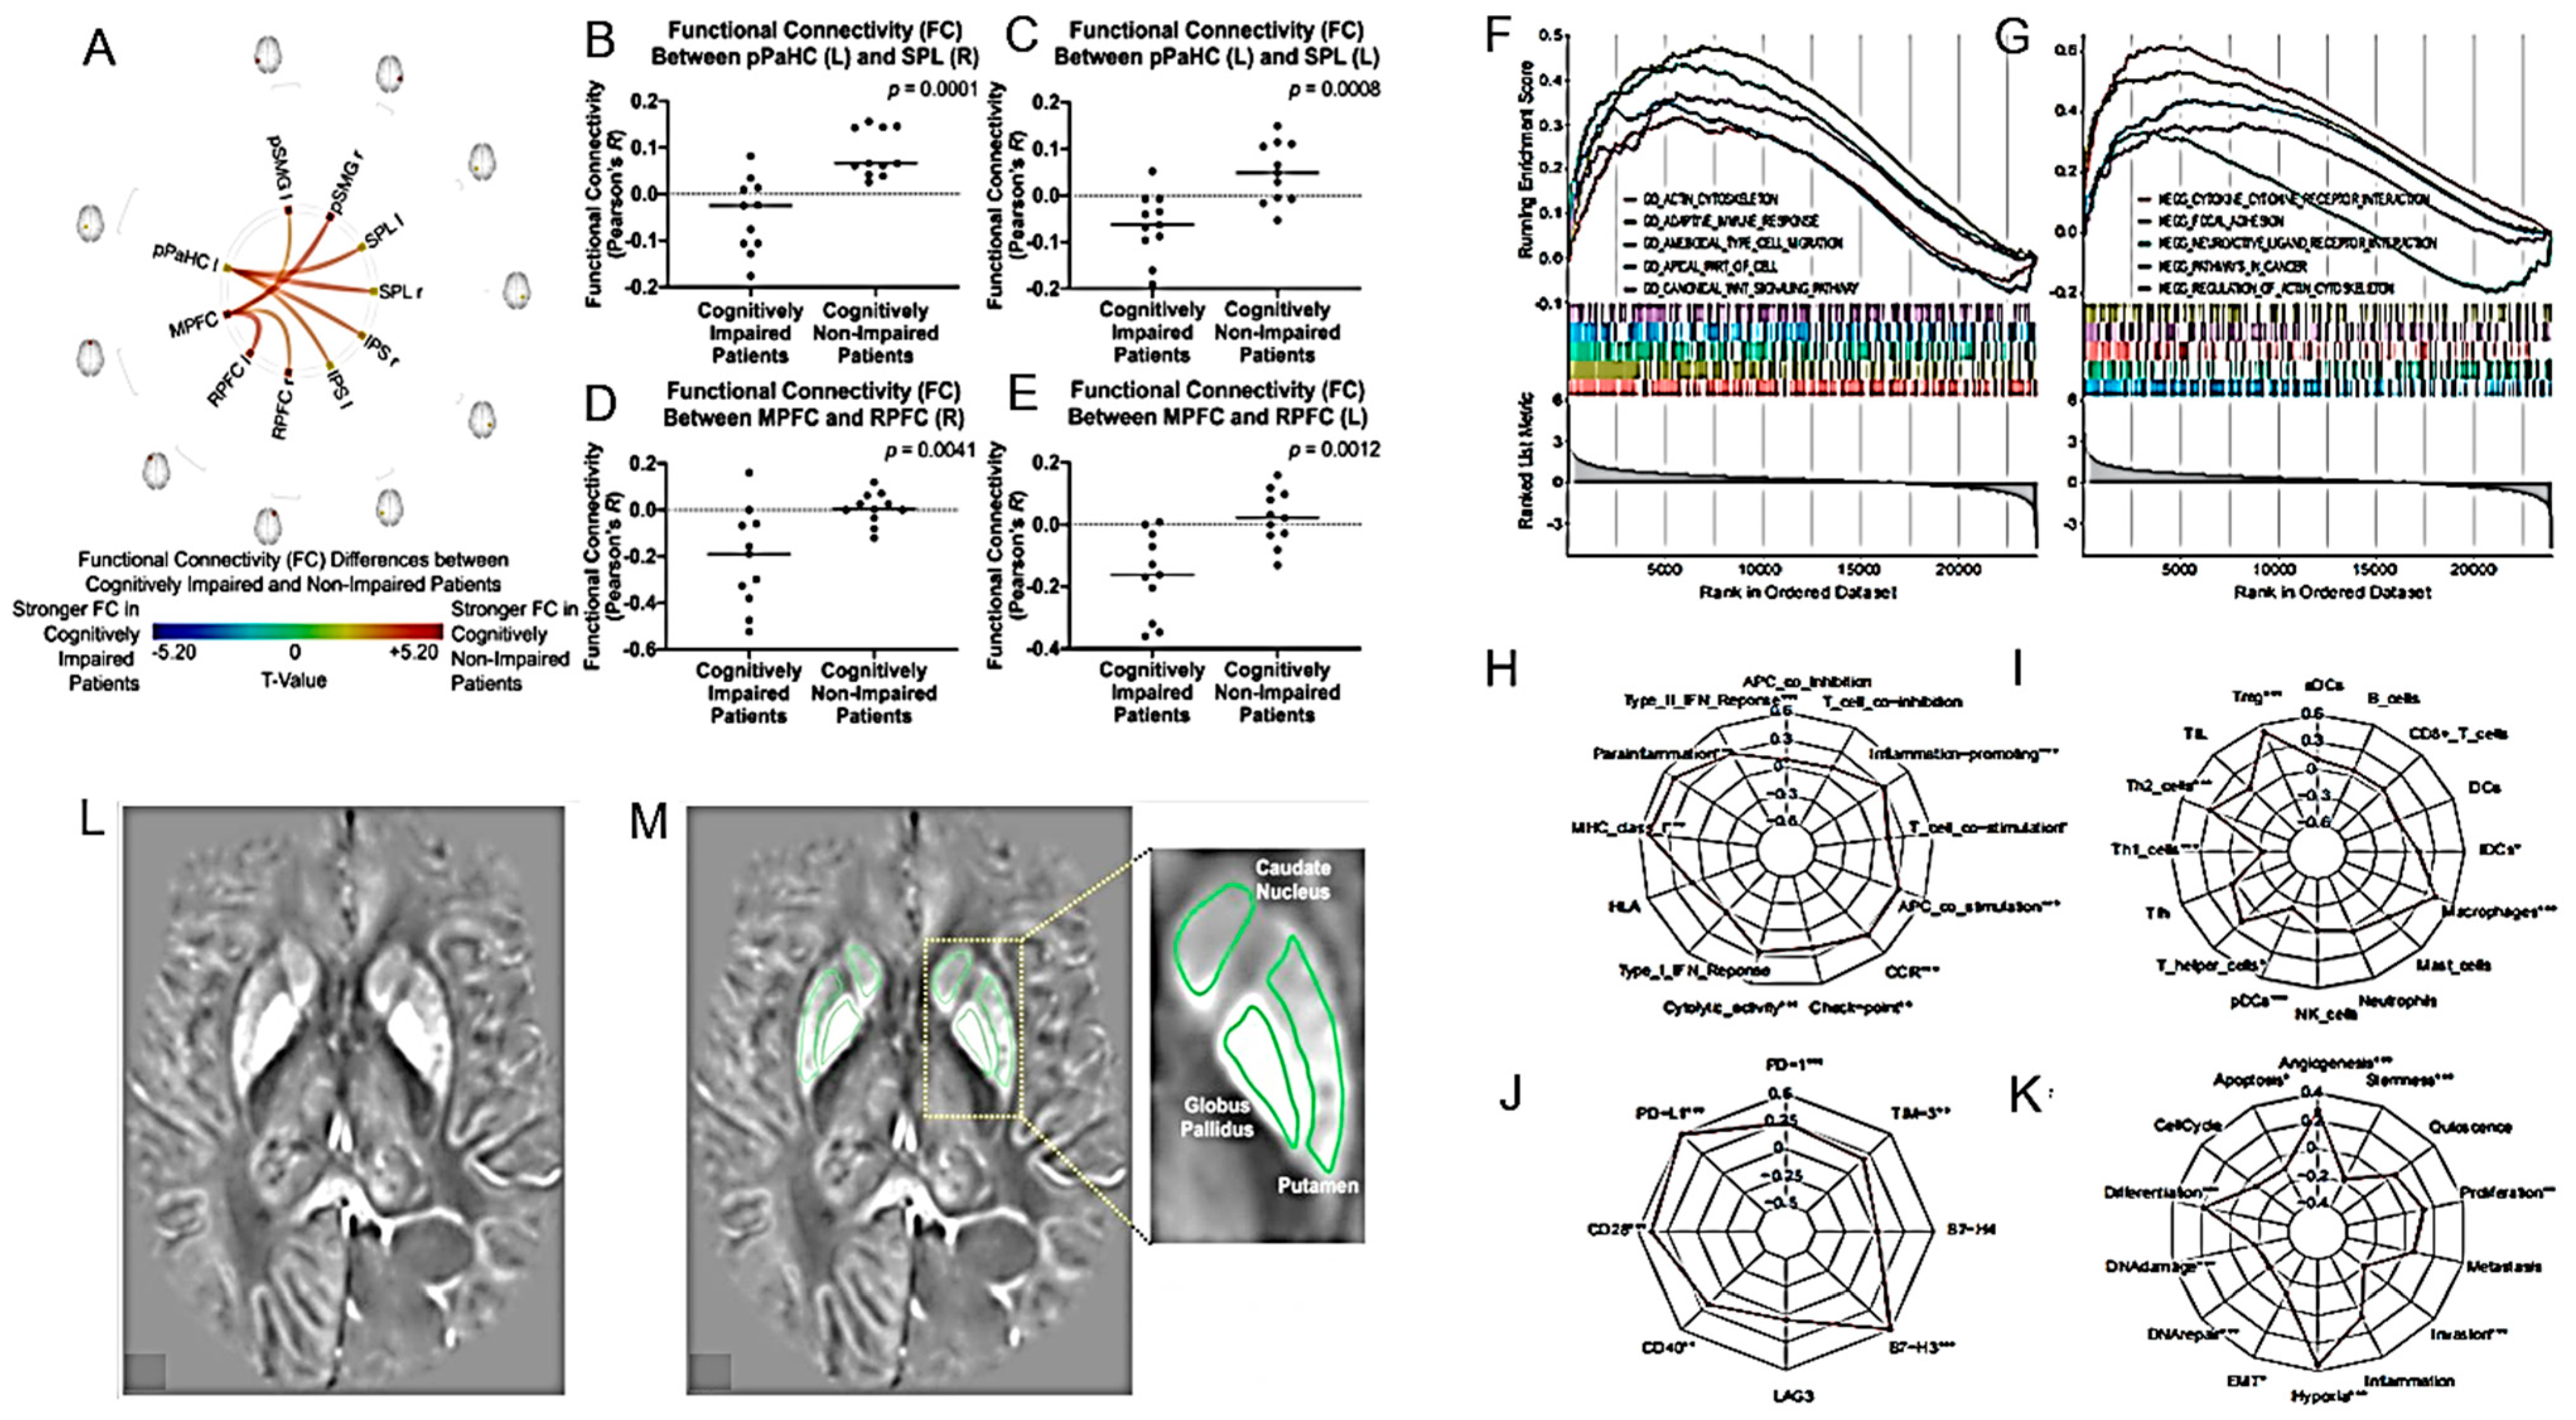

| rs-fMRI may identify neural correlates for cognitive and daily functioning in glioma patients. | 22 patients with diffuse gliomas who completed treatment within the past 10 years. | [110] |

| Basal ganglia iron levels as a biomarker in glioma prognosis and treatment. | 59 patients with brain lesions. | [113] |